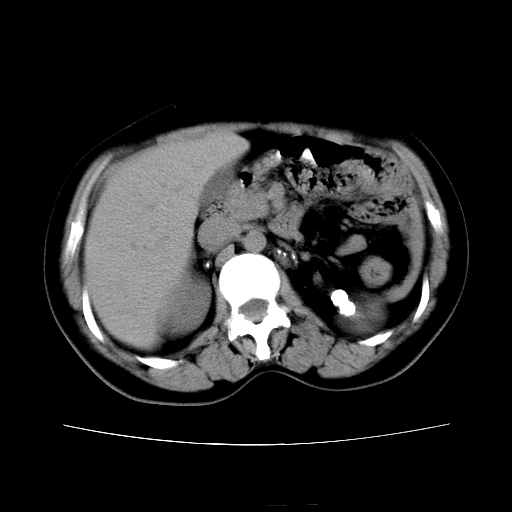

女45y多次(7次)碎石,结果不理想!曾碎石后尿出小碎石,仍腰痛,要求ct,其它不详.本人更倾向于钙化斑!无肾实质破坏,积水等提示集合系统无梗阻.另外腹腔多处钙化.是否结核后改变!谢谢赐教!

1)双肾结石。2)脾脏钙化灶。3)腹膜后多发淋巴结钙化。

尿路结石与腹部淋巴结钙化共存,建议v尿路造影检查,免得钙化灶冤枉为结石受罚。

考虑双肾结石,肾脏实质无破坏表现,没有结核病史,不考虑肾结核,